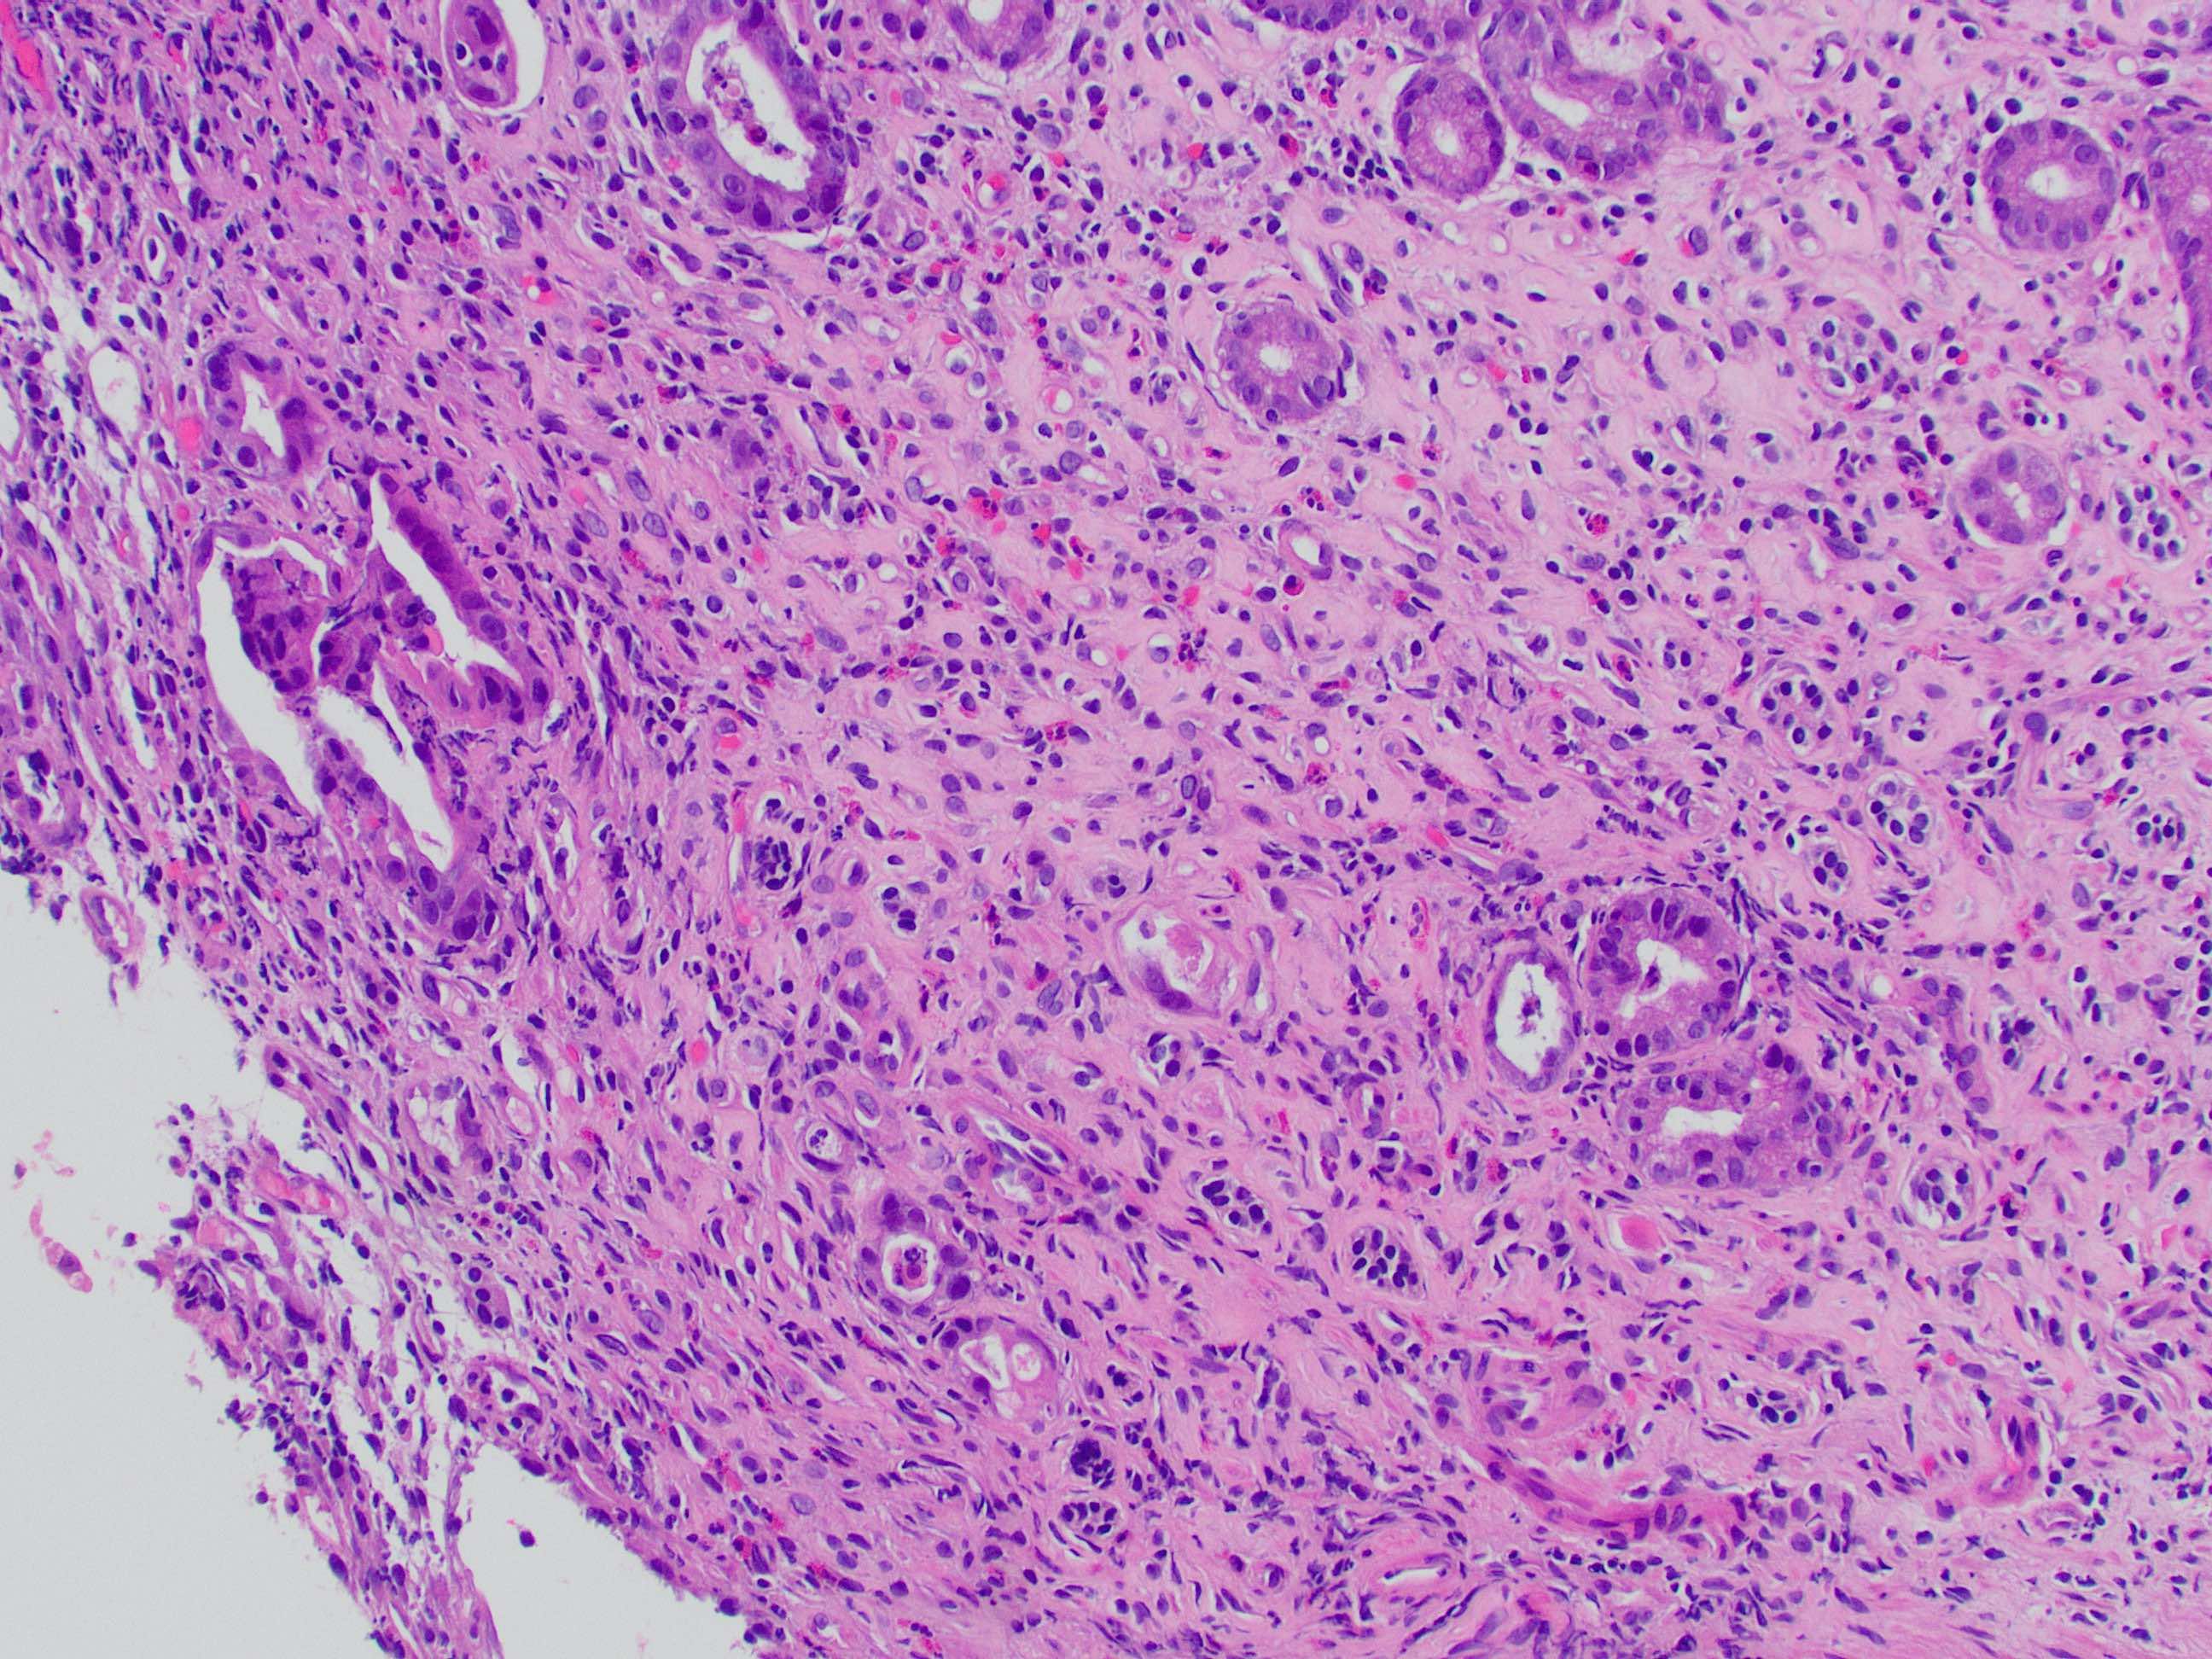

That covers the basics! Here is a direct side-by-side before and after editing in GIMP:

That covers the basics! Here is a direct side-by-side before and after editing in GIMP: